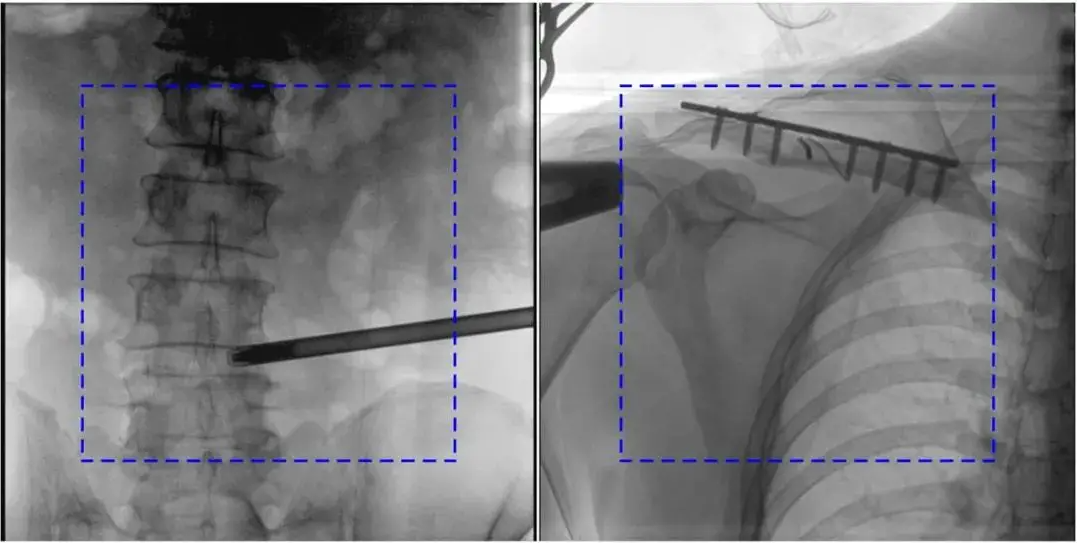

AEC模式下,金屬植入物或患者體位偏離視野中心可能導致曝光不足或過度。

解決辦法:手動調整曝光參數,確保感興趣區域位于視野中央;避免金屬干擾,必要時調整患者體位。